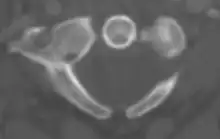

Atlas from above

The atlas's chief peculiarity is that it has no body,[3] which has fused with the next vertebra.[4] It is ring-like and consists of an anterior and a posterior arch and two lateral masses.

Vertebral foramen

Just below the medial margin of each superior facet is a small tubercle, for the attachment of the transverse atlantal ligament which stretches across the ring of the atlas and divides the vertebral foramen into two unequal parts:

- the anterior or smaller receiving the odontoid process of the axis

- the posterior transmitting the spinal cord (medulla spinalis) and its membranes